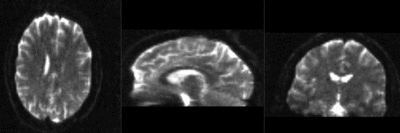

RegLib C32 RegisteredAffine.gif T1 registered to DTI baseline : Affine only(click to enlarge)